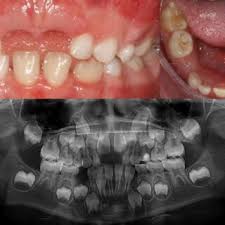

치주염 진단과 검사

치주염(Periodontitis)을 진단하고 검사하는 과정은 치과 전문가에 의해 수행되며 다양한 절차와 도구를 사용합니다. 아래에 치주염 진단과 검사에 대해 자세히 설명하겠습니다:

2. 치아 및 잇몸 검사: 치과 의사는 환자의 치아와 잇몸을 시각적으로 검사합니다. 이 과정에서 치과 거울과 탐진기(프로브)를 사용하여 치아 주위 잇몸의 충혈, 부풀음, 치아 이동 및 치주주머니의 형성 여부를 확인합니다.

3. 치주주머니 측정: 치주염의 진행 정도를 판단하기 위해 치주주머니의 깊이를 측정합니다. 탐진기를 사용하여 치주주머니의 깊이를 측정하고, 이것은 치주염의 정도를 판단하는 중요한 지표 중 하나입니다. 정상적인 치주주머니의 깊이는 3 밀리미터 미만이며, 치주염이 진행되면 깊이가 증가합니다.

4. X-레이 검사: 치주염 진단에는 치아 주변 뼈의 손상 정도를 평가하기 위해 X-레이 검사가 사용될 수 있습니다. 이를 통해 의사는 뼈 손상이 어느 정도인지 확인하고 치주염의 정확한 진행 정도를 평가할 수 있습니다.

1. 치아 손실: 치주염은 치아 주변 조직의 파괴를 초래하며, 치주주머니의 깊이가 증가할수록 치아를 지지하는 뼈가 손상될 수 있습니다. 이로 인해 치아가 이동하거나 흔들릴 수 있으며, 치아 손실의 주요 원인 중 하나가 됩니다.

2. 뼈 손상: 치주염은 치아 주변 뼈에 손상을 일으킬 수 있으며, 이로 인해 뼈의 감소와 조직의 파괴가 발생할 수 있습니다. 심한 경우, 이로 인해 치아를 잃는 결과로 이어질 수 있습니다.

4. 파노라마각도(치주염각도) 감소: 치주염이 진행되면 치아 주변의 조직이 파노라마각도(치주염각도)를 감소시키며, 이는 치아를 더 어렵게 관리하게 만들고 칫솔이나 치실로 적절히 청소하기 어렵게 합니다.